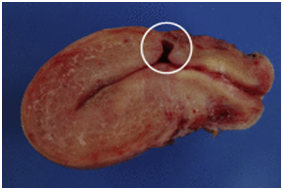

Figure 1 Courtesy ref no-6-Sagittal view of a frozen section from a hysterectomy specimen. A deep anterior defect covered with a thin layer of myometrium (white circle) can be observed at the level of the supposed site of CS.